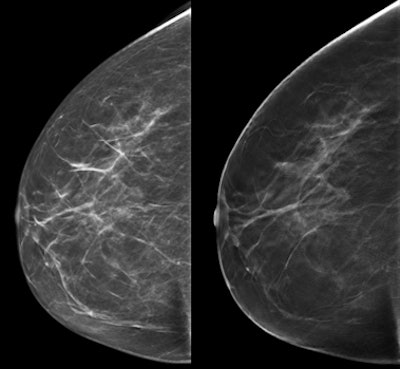

An example of screen-detected invasive carcinoma (dorsal positioning). It was difficult to see on 2D (left) but clearly visible on DBT (right). All images courtesy of Dr. Hildegunn Aase and Solveig Hofvind, PhD.DBT vs. mammography